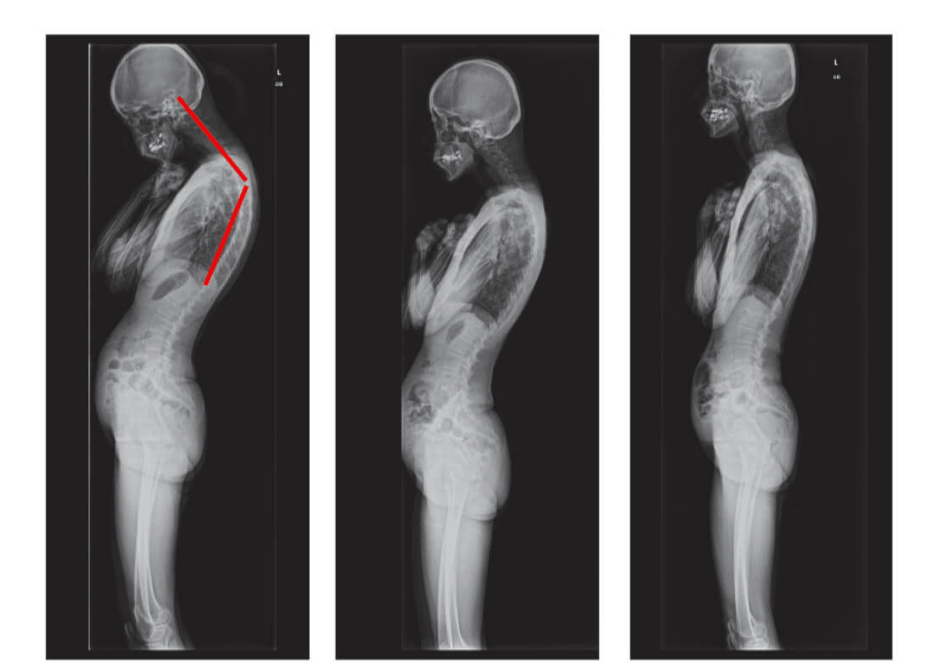

Wanita, 62 tahun. Pergeseran tulang belakang yang parah. "Jointlite" berhasil memulihkan tulang belakang sepenuhnya dalam 90 hari.

Pria, 37 tahun. Koreksi total postur tubuh dengan "Jointlite" selesai dalam 1,5 bulan.

Wanita, 51 tahun. "Punggung bungkuk janda" dan deformasi tulang belakang. Benjolan sepenuhnya hilang dalam 60 hari penggunaan "Jointlite".